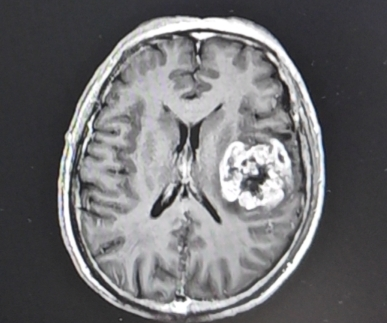

术后CT

术后,患者很快苏醒,右侧肢体肌力无明显下降,感觉及运动良好,语言功能无减退,手术圆满成功,术后复查肿瘤全切。病理结果回报提示:胶质母细胞瘤。